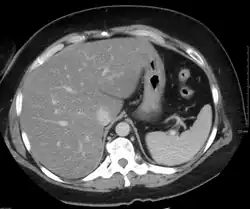

Imaging studies are often obtained during the evaluation process. Ultrasonography reveals a "bright" liver with increased echogenicity. Pocket-sized ultrasound devices might be used as point-of-care screening tools to diagnose liver steatosis.[30] Medical imaging can aid in diagnosis of fatty liver; fatty livers have lower density than spleens on computed tomography (CT), and fat appears bright in T1-weighted magnetic resonance images (MRIs). Magnetic resonance elastography, a variant of magnetic resonance imaging, is investigated as a non-invasive method to diagnose fibrosis progression.[31]

Histological diagnosis by liver biopsy is the most accurate measure of fibrosis and liver fat progression as of 2018.[8] Conventional imaging methods, such as ultrasound, CT and MRI, are not specific enough to detect fatty liver disease unless fat occupies at least 30% of the liver volume.[32]